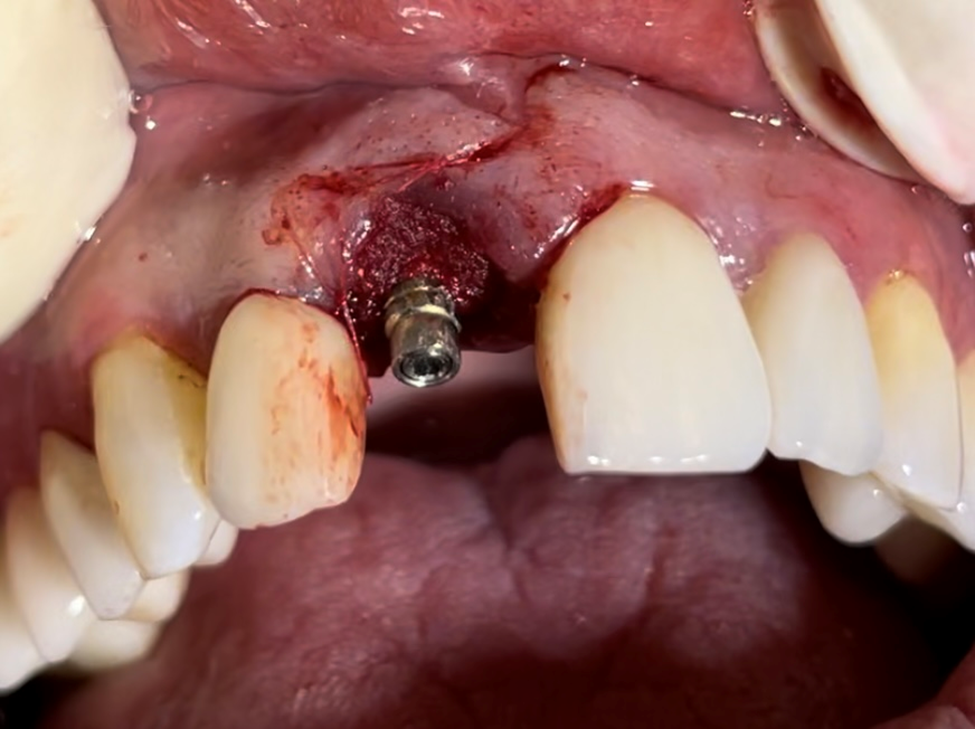

O GAP foi preenchido com biomaterial Extra Graft, que foi facilmente condensado para dentro do alvéolo, no espaço entre o implante e a parede vestibular (Figura 6). Uma membrana de colágeno foi posicionada sobre o biomaterial, para protegê-lo na execução dos procedimentos protéticos (Figura 7).